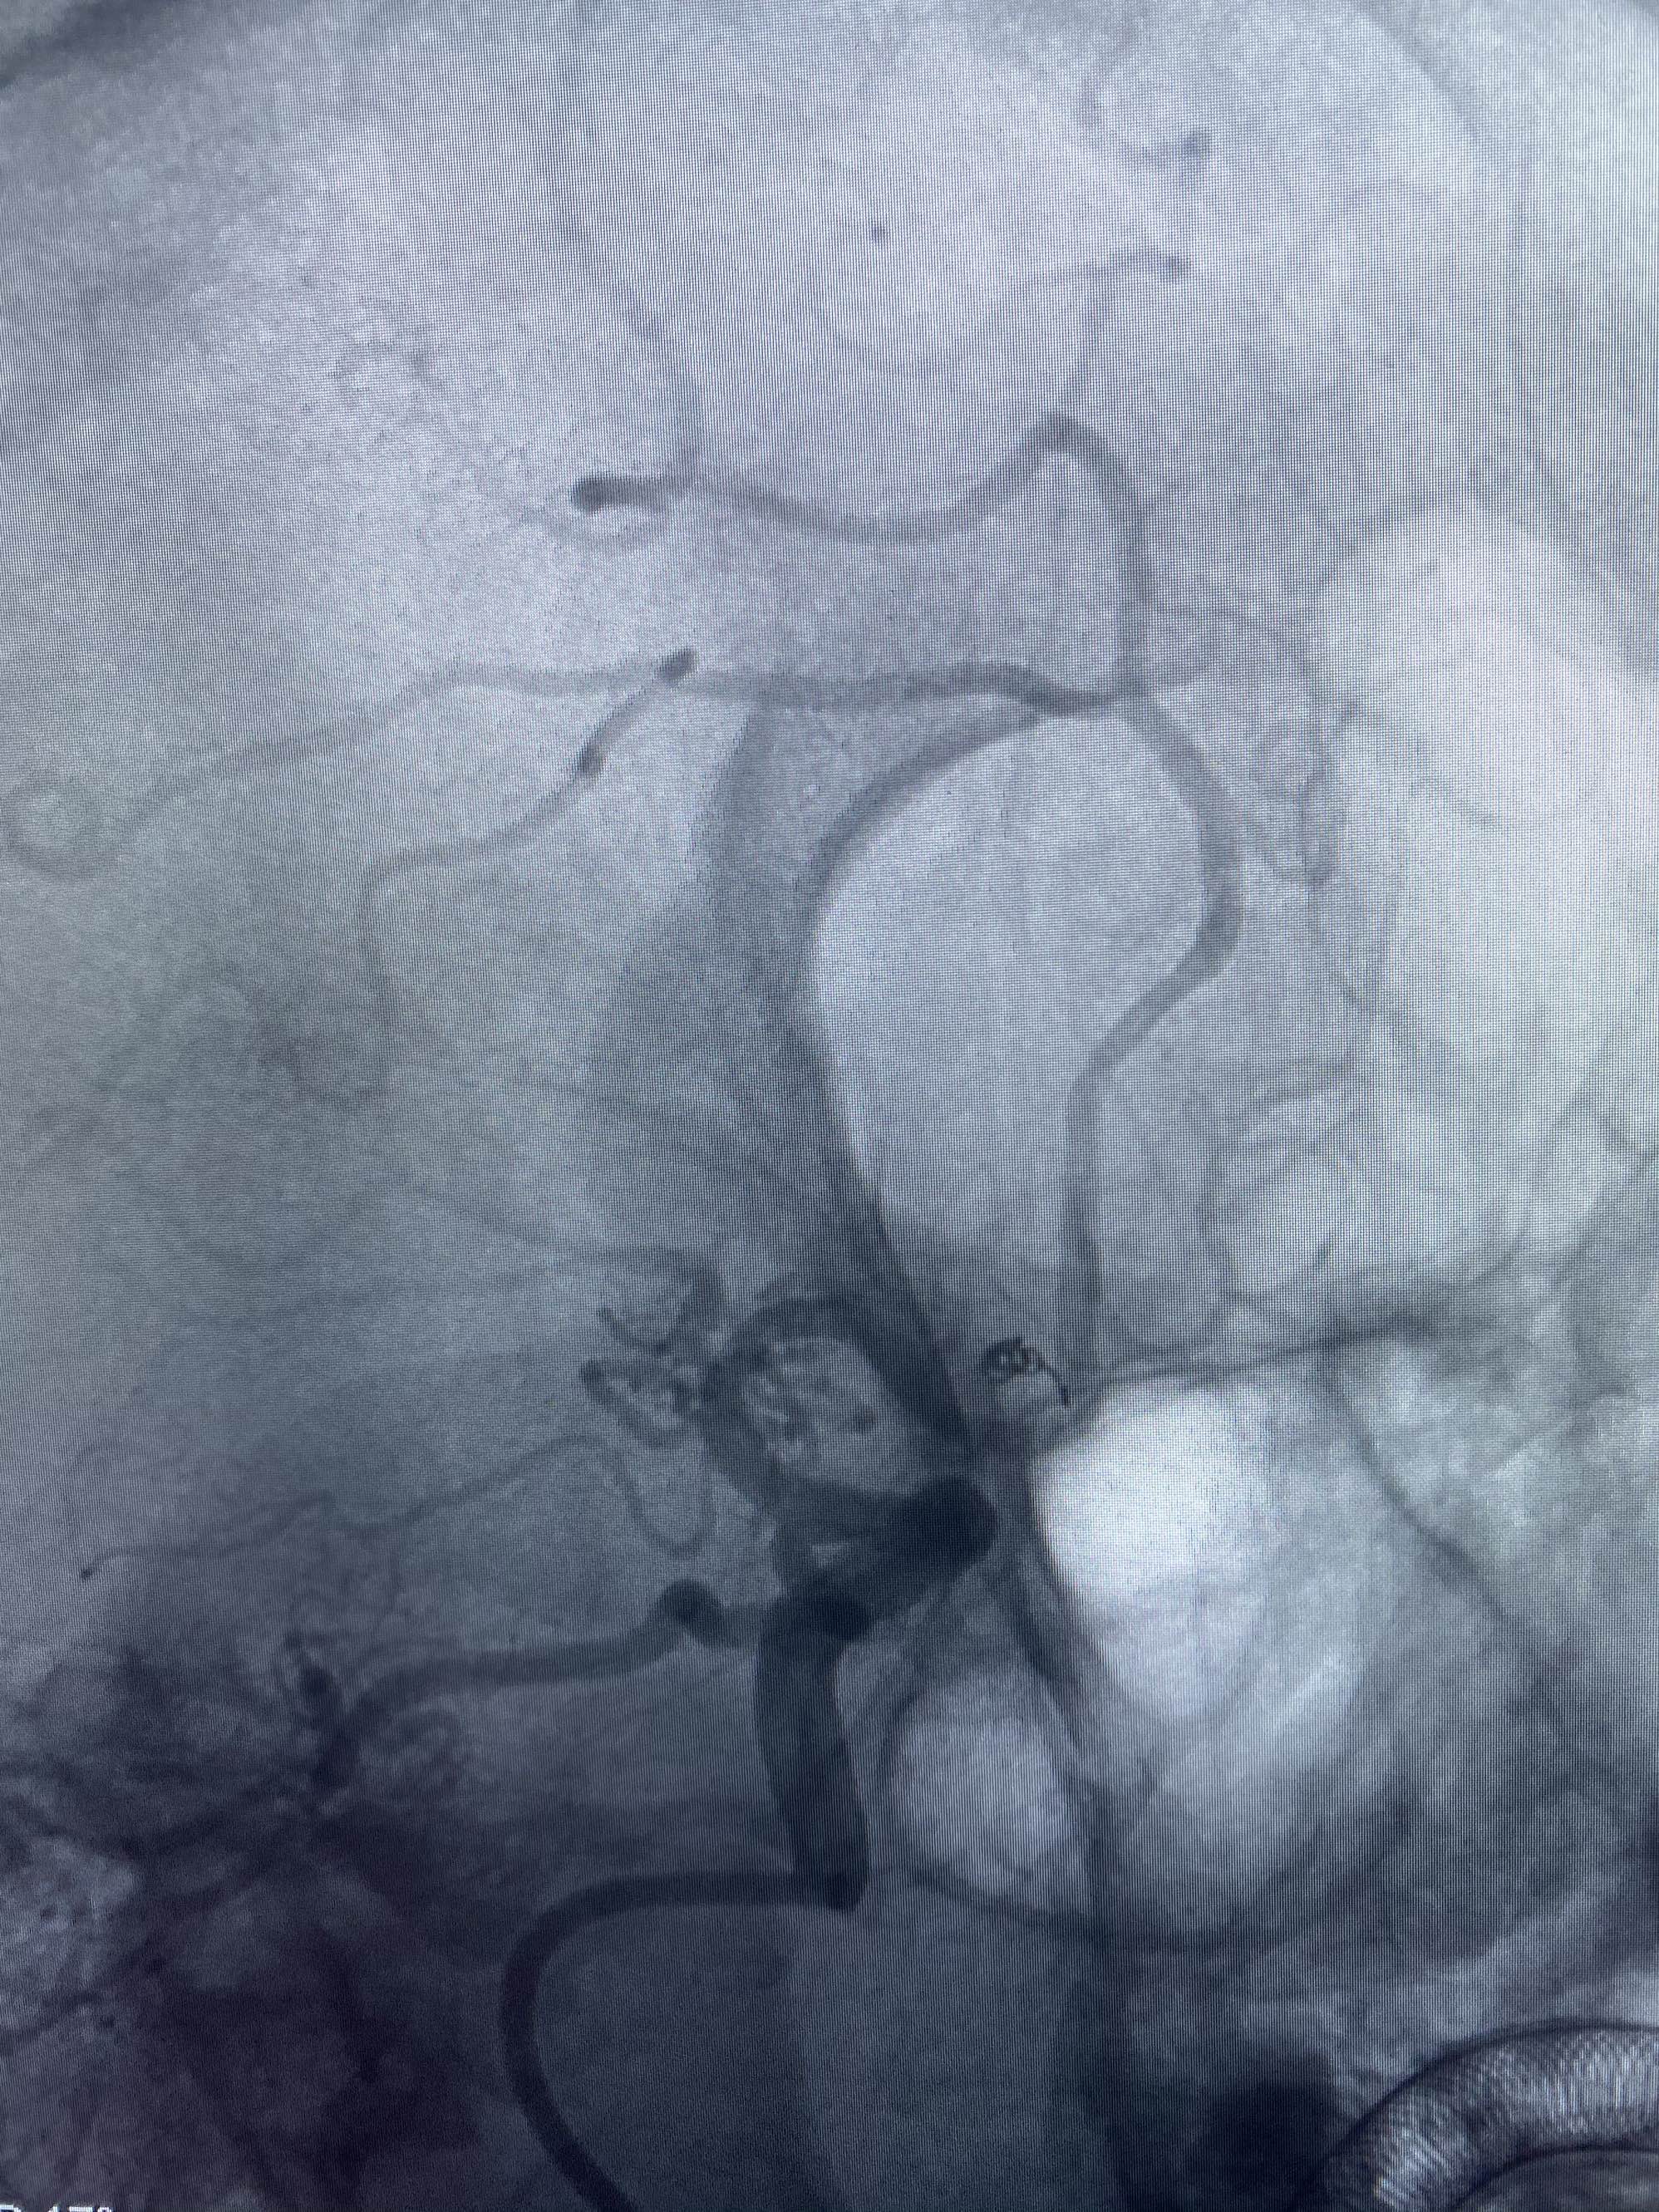

MLS,M79Y,sah,双侧MCA烟雾病,Heubner返动脉瘤,前交通段开窗,细支发出Heubner返动脉,瘤颈细长,瘤颈口比微导管细,弹簧圈2mmx3cm“隔山打牛”填塞治愈,Heubner返动脉保留。

该患者术后2天观察神志清楚,四肢活动正常。